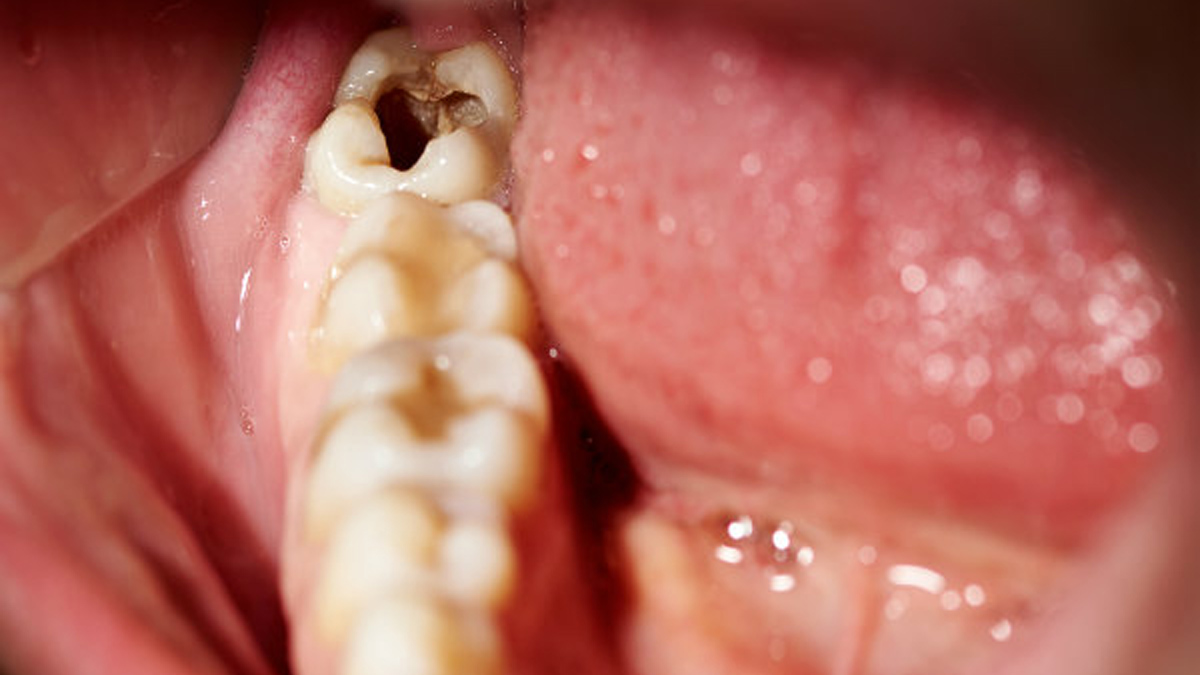

ആദ്യം ഒരു കറുത്ത പുള്ളി, പതിയെ പതിയെ ദ്വാരം: ഇതെല്ലാം കഴിക്കുന്നവര് അറിഞ്ഞിരിക്കണം

പല്ലിന്റെ ആരോഗ്യം എപ്പോഴും ഒരു വെല്ലുവിളി തന്നെയാണ്. അതില് പ്രധാനമായും സംഭവിക്കുന്ന പ്രതിസന്ധികള് എന്ന് പറയുന്നത് എപ്പോഴും പല്ലിലെ പോടും, വായ്നാറ്റവും മോണരോഗവും പോലുള്ളതാണ്. എന്നാല് ഈ പ്രശ്നം നമ്മള് അല്പമൊന്ന് ശ്രദ്ധിച്ചാല് പരിഹരിക്കാന് സാധിക്കുന്നതും ആണ് എന്നതാണ് സത്യം. തിളക്കമുള്ള പുഞ്ചിരിക്കും പാല്നിറമുള്ള പല്ലിനും വേണ്ടി ചില കാര്യങ്ങള് ശ്രദ്ധിക്കാവുന്നതാണ്. പലപ്പോഴും നല്ല ദന്താരോഗ്യം നിലനിര്ത്തുക എന്നത് അല്പം കഷ്ടപ്പാടുള്ള പണി തന്നെയാണ്. എപ്പോഴും ദന്താരോഗ്യത്തെ സംരക്ഷിക്കുന്നതിന് വേണ്ടി ശ്രമിക്കുമ്പോള് അറിഞ്ഞിരിക്കേണ്ട ചിലതുണ്ട്.

ഒഴിവാക്കേണ്ട ഭക്ഷണങ്ങള് തന്നെയാണ് അതില് ആദ്യം വരുന്നത്. പല്ലിലെ പോടുകള്ക്ക് കാരണമാകുന്നതും പല്ല് ക്ഷയിക്കാന് കാരണമാകുന്നതും എല്ലാം ഇത്തരത്തില് ചില ഭക്ഷണങ്ങള് തന്നെയാണ്. പല്ല് ക്ഷയിക്കാന് കാരണമാകുന്ന ആസിഡുകള് ഉത്പാദിപ്പിക്കപ്പെടുമ്പോഴാണ് ഇത്തരത്തില് സംഭവിക്കുന്നത്. ഇത് പല്ലിലെ ഇനാമലിനെ പ്രശ്നത്തിലേക്ക് എത്തിക്കുന്നു. ഇത് വഴി പല്ലില് പോടുകളും ഉണ്ടാവുന്നു. പല്ലിനെ പോടില് നിന്ന് സംരക്ഷിക്കുന്ന ചില ഭക്ഷണങ്ങള് ഉണ്ട്. അവ എന്തൊക്കെയെന്ന് നോക്കാം.

എപ്പോഴും ആദ്യം ശ്രദ്ധിക്കേണ്ടത് പഞ്ചസാര അടങ്ങിയ മിഠായികളും ലഘുഭക്ഷണങ്ങളും ഒഴിവാക്കുക എന്നതാണ്. ഇത് പല്ലുകള് ക്ഷയിക്കുന്നതിനും പല്ലില് പോടുകള് വലുതാവുന്നതിനും കാരണമാകുന്നു. ഇത്തരം മധുരപലഹാരങ്ങളിലെ പഞ്ചസാര പല്ലില് ഒട്ടിപ്പിടിക്കുകയും പറ്റിപ്പിടിച്ചിരിക്കുകയും ചെയ്യുന്നു. ഇത് പല്ലിലെ ഇനാമലിനെ നശിപ്പിക്കുന്ന തരത്തിലുള്ള ആസിഡുകള് ഉത്പാദിപ്പിക്കുന്നു. അതുകൊണ്ട് തന്നെ പല്ലില് പതിയെ പതിയെ കറുത്ത കുത്തുകളും അത് പിന്നീട് പോട് പരുവത്തിലേക്ക് മാറുകയും ചെയ്യുന്നു.